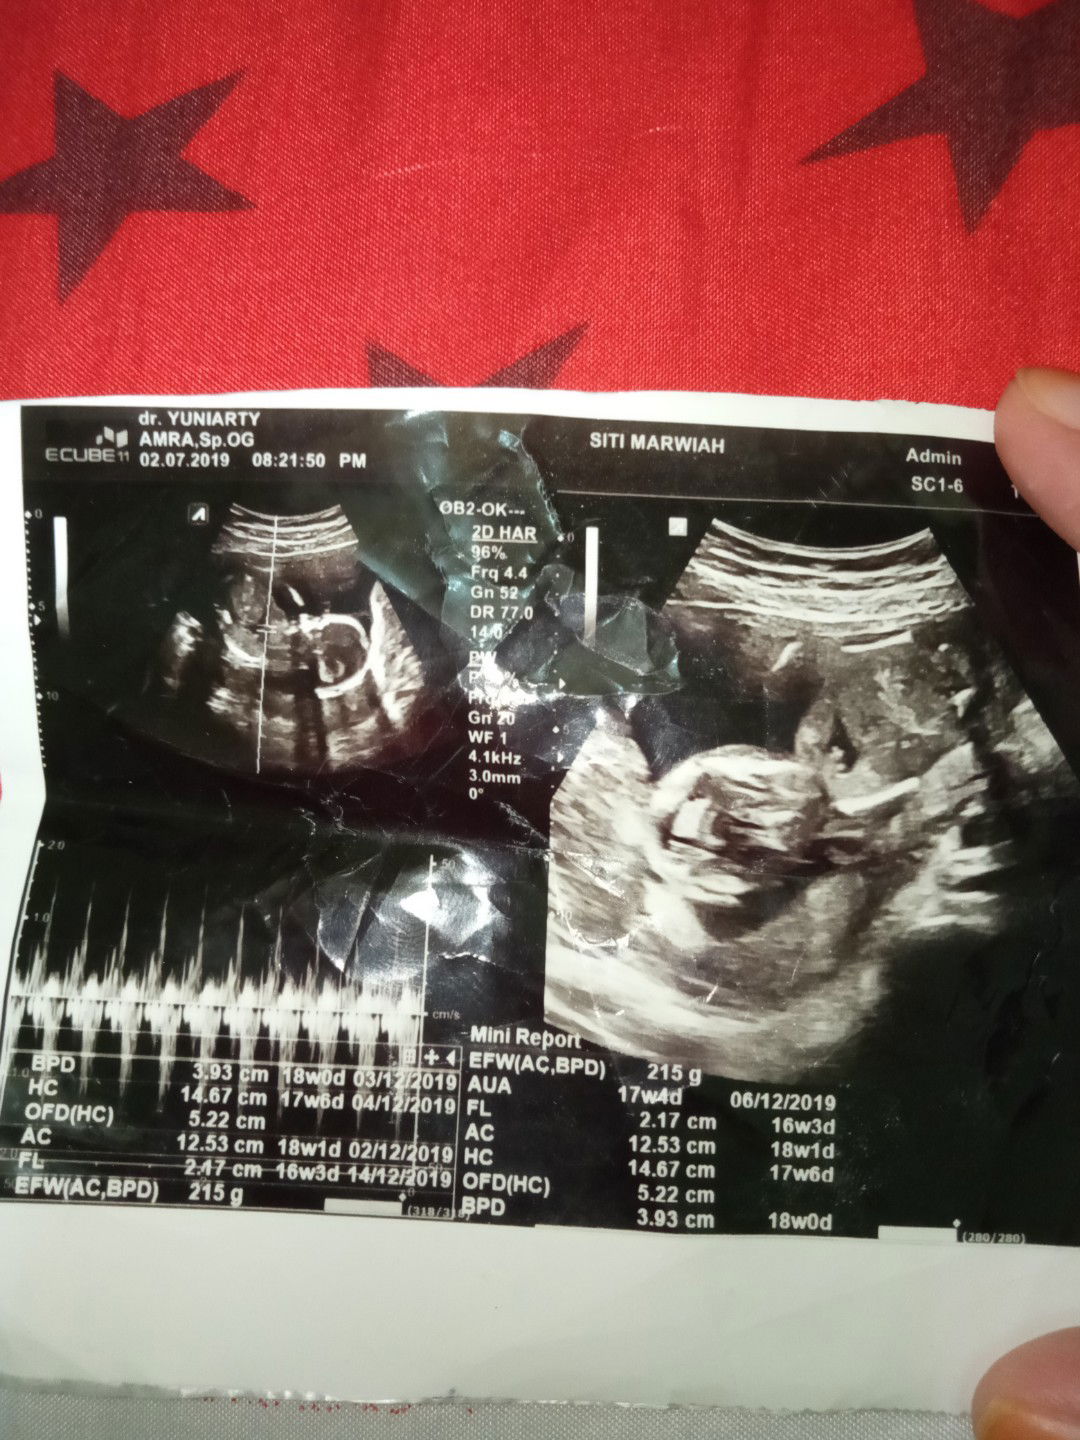

USG 4 bulan kmrin

????sdh tdk sabar pengen ketemu dngmu nak